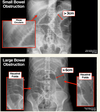

162

what are these lines in these bowl obstructions. where are each of the obstructions?

what is a normal diameter ofL small intestine, large intestine, caecum